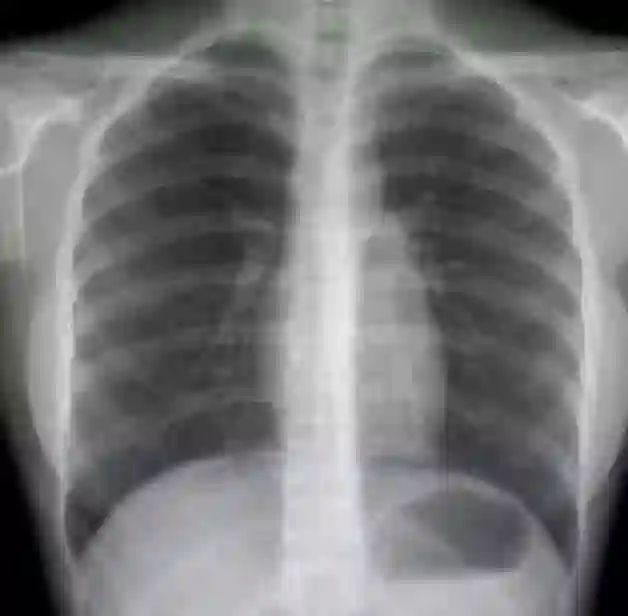

肺结节AI辅助诊断

肺癌,在我国的发病率、死亡率极高,伤害着无数家庭。在我国每年都有近60万人死于肺癌。肺癌防治的重要手段是早期筛查,其中胸部低剂量CT是国际公认的有效手段。而在如今传统的阅片模式中,医学影像面临医疗从业人员短缺,人工分析模式精准度受限,以及基层医院医疗机构诊断水平参差不齐,高年资医生匮乏,易出现漏诊、误诊等问题。

现阶段市场中的人工智能肺CT产品已经实现了肺结节的检出功能,可支持包括:实性结节、磨玻璃结节、形态不规则的大结节、血管旁结节、肺门区结节等。支持提供量化信息检测如自动测量病灶的长径、短径、CT值、体积等参数。支持提供定性信息检测如病灶密度:实性、部分实性、磨玻璃、钙化,以及病灶良恶性等级分类:良性、疑似良性、恶性、疑似恶性。另外支持多种伴随征象的检出,如边界模糊、分叶、毛刺、胸膜牵拉、血管集束等。此外还有肿块、斑片、网影、条索影、气胸、胸腔积液等病变检出。部分产品还含有胸部骨质病变筛查功能,自动检出骨折,支持3D的可视化帮助医生定位,进行全面智能分析与诊断。

胸部平片AI

数字化X光成像(CR/DR)是医疗机构普及率最高的设备之一,基层医疗机构普遍都拥有该设备。尤其是DR,成像速度快、辐射剂量低、空间分辨率高且设备成本低,因此无论是常规体检,还是门诊疾病初步判断,或是入院查体,平片都是最常见用的影像学检查手段。其中胸部平片是检查量最大、应用最广泛的部位之一。

目前国内外胸部平片AI产品功能主要集中在异常征象的检出。在2018年的北美放射学年会上参展的20家左右的医学影像AI公司有约一半展出了各自的产品。其中产品形态较为成熟的公司有EIRL公司(日本)、QURE公司(美国)、VUNO(韩国)、LUNIT(韩国)。但截止到目前为止还没有公司通过了FDA认证。国内进行胸部平片AI产品的研发机构不多,主要有深睿医疗、推想科技,视见科技等。